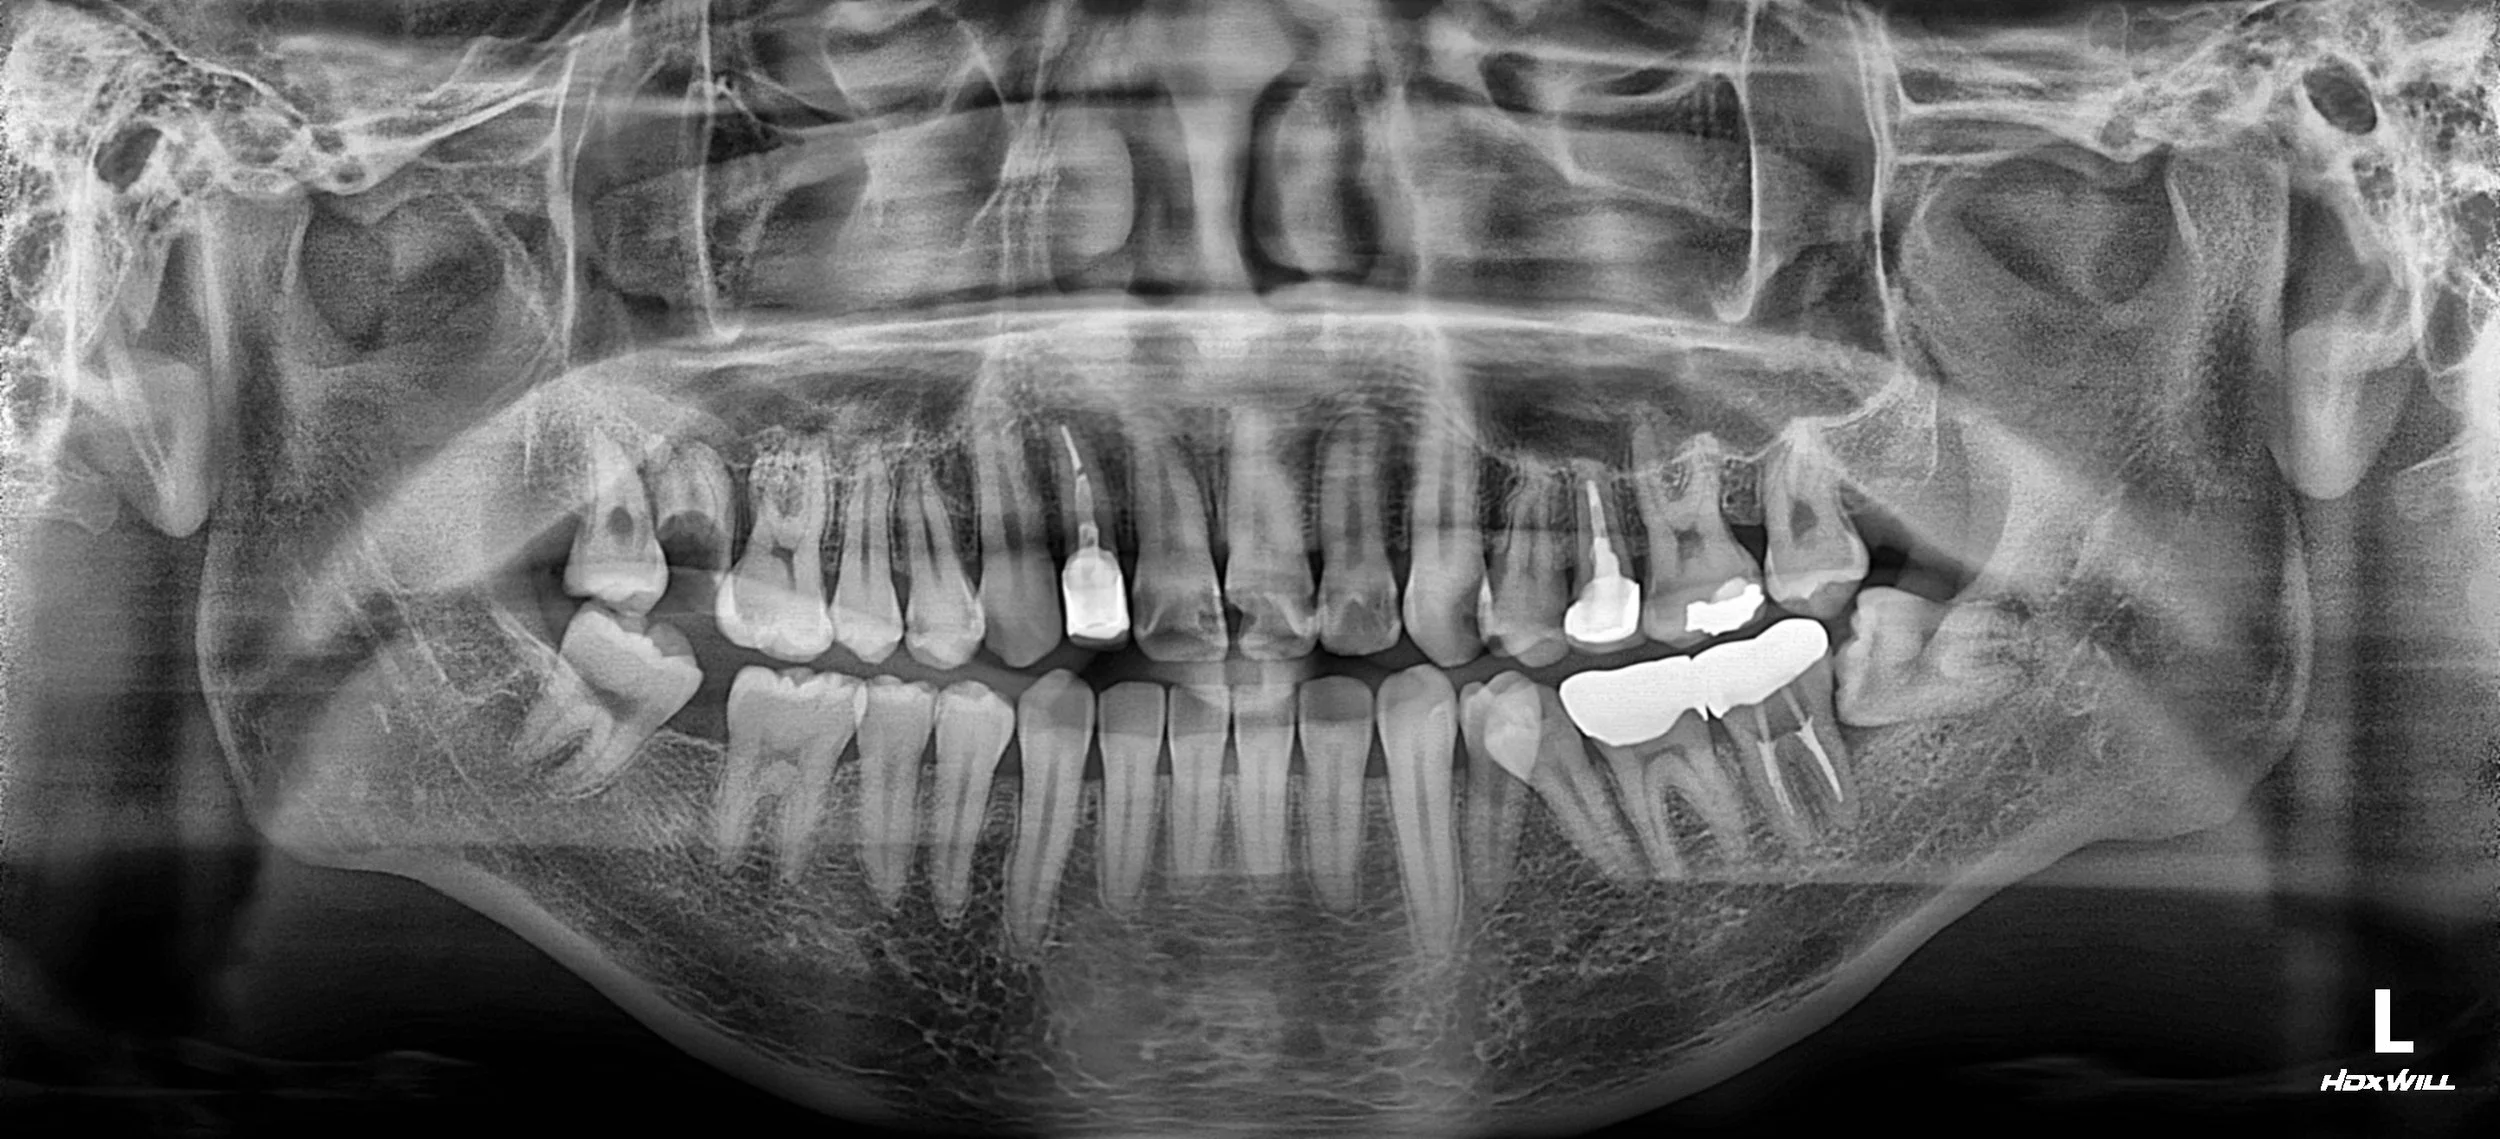

OPG - BEFORE

A male patient in his 20s presented with extensive dental caries across multiple teeth and a significantly compromised occlusal relationship. The primary clinical concerns were:

• Generalized Rampant Caries: Multiple teeth required urgent restorative and endodontic intervention.

• Mandibular Deviation & Midline Shift: The patient exhibited a noticeable shift in the dental midline and mandibular deviation, leading to both functional instability and aesthetic disharmony.

1. Infection Control & Endodontics: Prioritizing the health of the pulp, multiple endodontic treatments were performed on teeth with deep caries. Hopeless decay was managed to create a clean foundation for the final prosthetics.